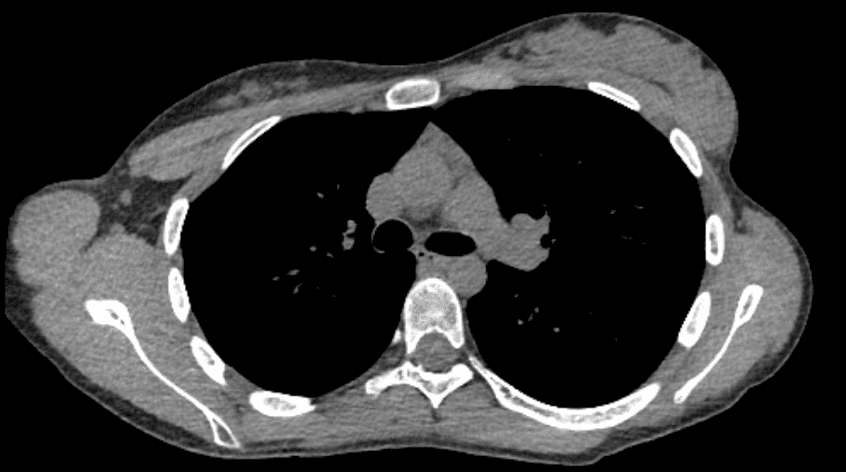

患者は胸部の断断層断層撮影を受け、優性胸腺腫なしに胸腺過形成が認められました。リンパ節腫脹や周囲構造への浸潤は伴っていませんでした。代表的な画像は図1に示されています。

図1。 優性胸腺腫なしの胸腺過形成を示す軸流コンピュータ断層撮影の代表的な断面図。